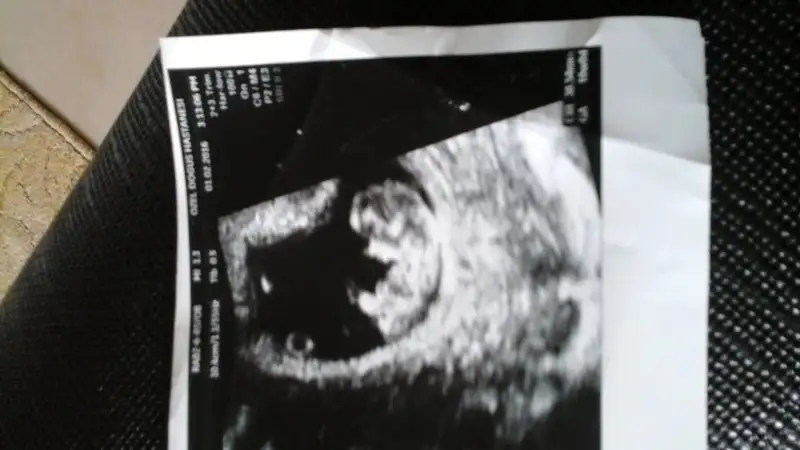

Ben de doktordan geldim kalbi atıyor dedi doktorum ama dinletmedi 8+3 dedi uyumlu yani satla çok şükür minnacık bi foto verdi elimeEki Görüntüle 1764966